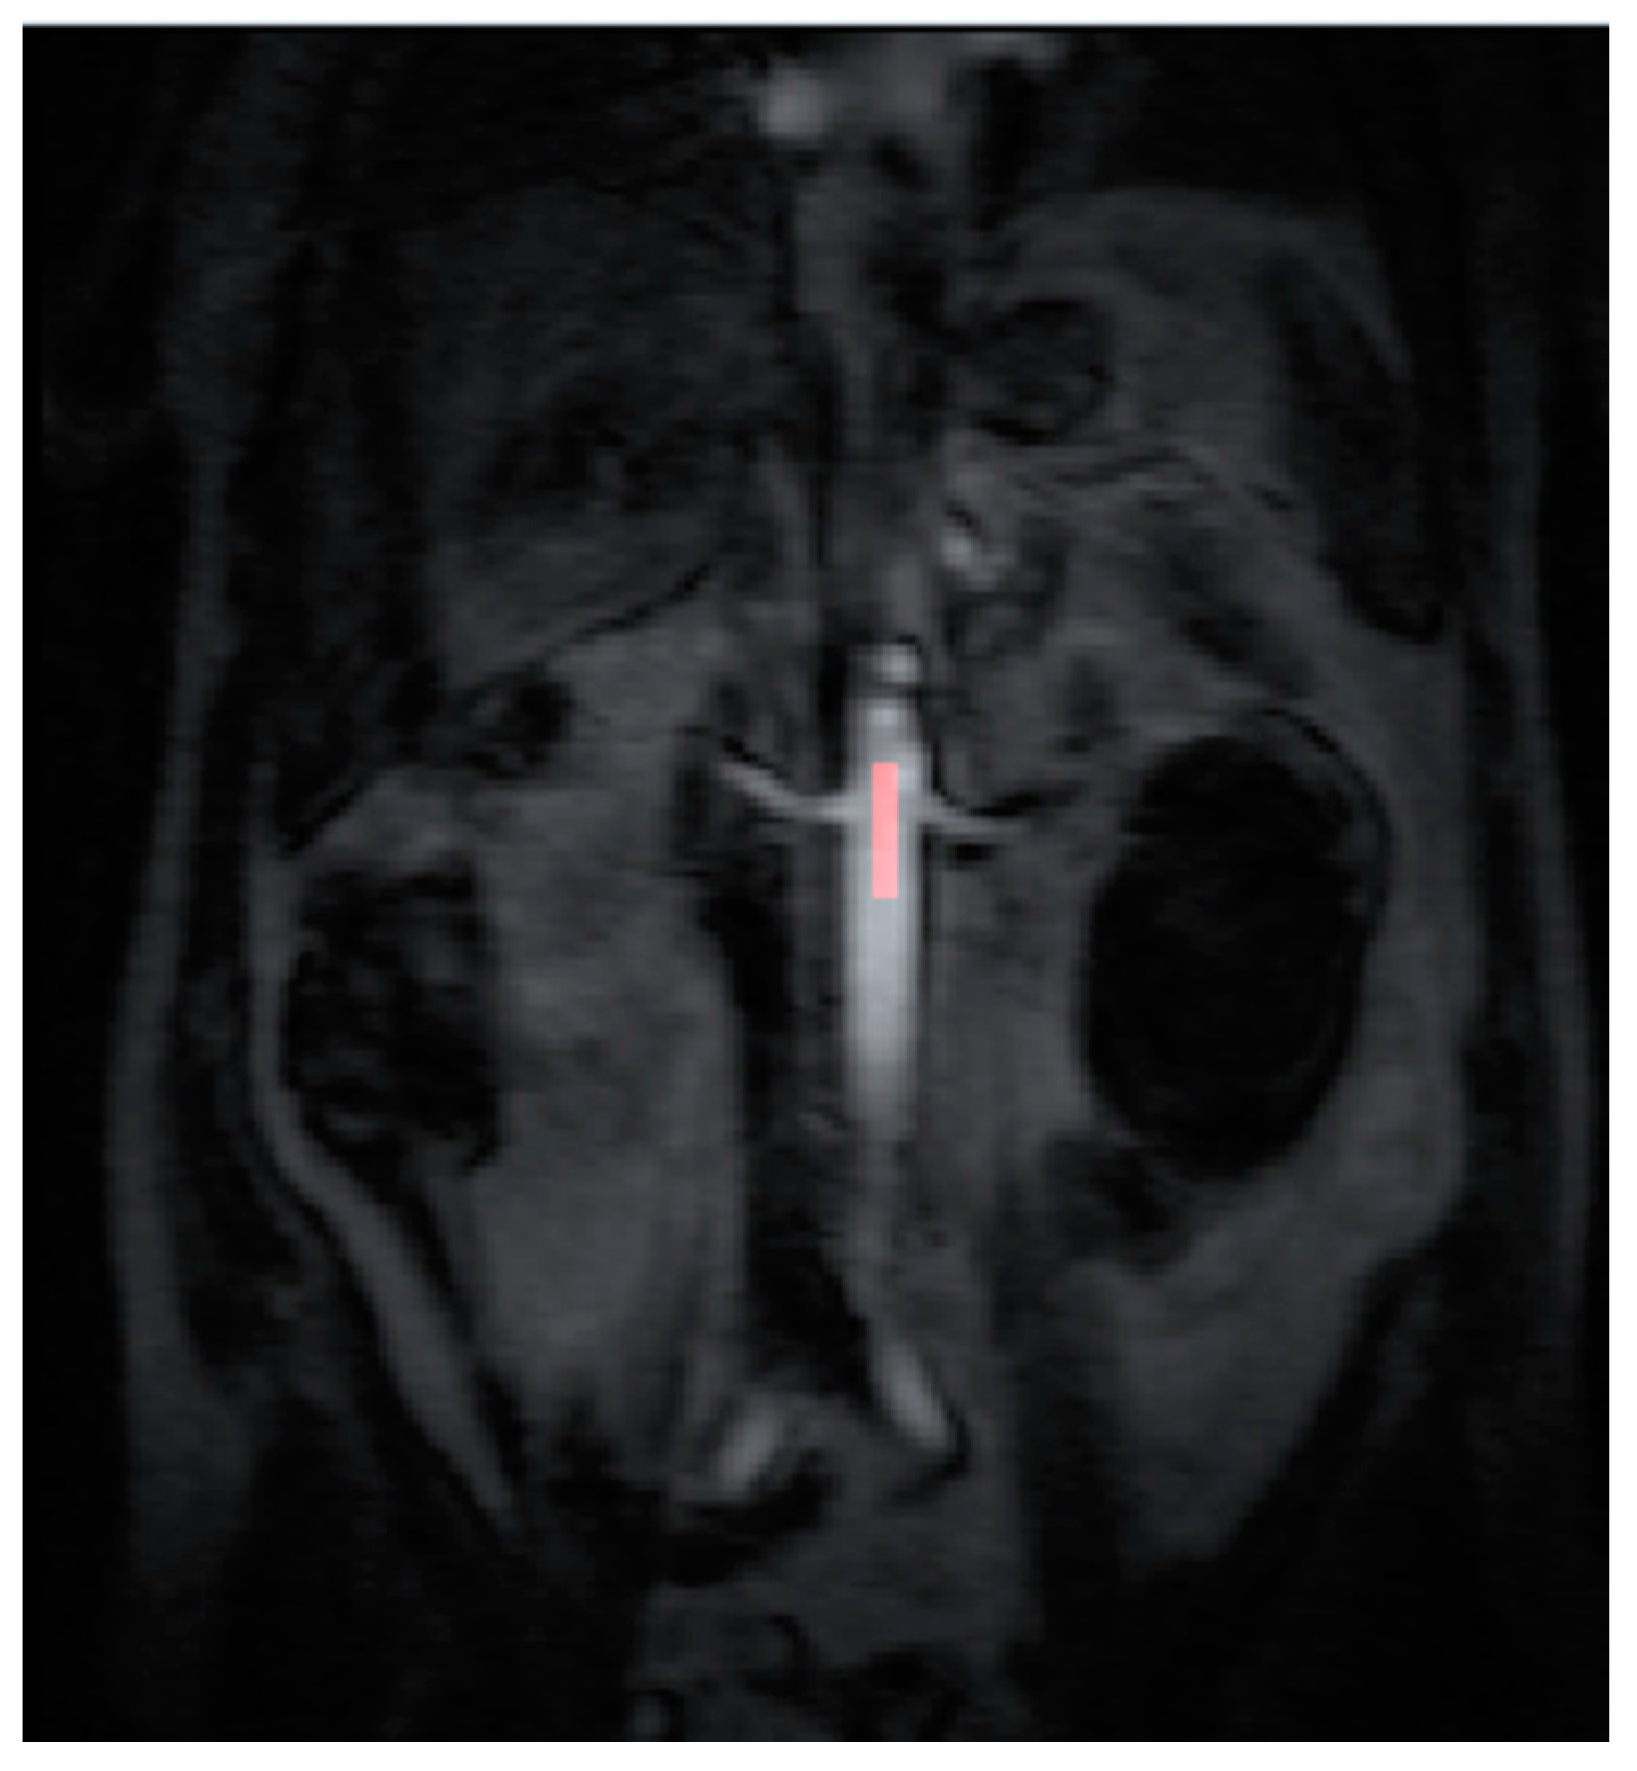

2.4. Data Post Processing

All the MR images were anonymized and post processing was performed offline by a single consultant radiologist with greater than 10 years of clinical experience (Dr Tze Min Wah). Images were uploaded into PMI 0.4 (Platform for Research in Medical Imaging Version 0.4 [13], which was running on a desktop PC. A standardized 4-voxel region was used to extract an arterial input function (AIF). This region of interest (ROI) was drawn inside the aorta at the approximate level of the origin of the vascular pedicles of the kidneys (Figure 1 and Figure 2).

Contrast agent concentration-time curves were approximated using relative change in signal (compared to baseline) against time [13]. To assist in identifying the tumour and drawing the ROI, a map of maximum contrast agent concentration was generated. Using the map, ROIs were drawn to encompass the renal tumour pre RFA (Figure 3) and the whole zone of ablation post RFA (Figure 4).

The pre RFA renal tumour and post RFA zone of ablation in every patient were saved and anonymized within the same dataset. Pre RFA, the ROI outlined the bright area which represents the enhancing renal tumour. In this cohort, some of the tumours had a cystic or necrotic component, but only the solid components were included in the ROIs. Post RFA, the ROI outlined the whole zone of ablation which is typically larger than the tumour to allow for the ‘surgical’ margin, this is the dark area on images that represents ‘dead’ renal tumour. If there is any bright area within the zone of ablation, this typically suggests area of enhancement and indicates that there is a viable renal tumour and this would be included with the ROI. This process was repeated for every slice containing pre RFA tumour and the post RFA zone of ablation. The regions for each slice were combined giving a volume of interest that covered the perfused renal tumour in the DCE dataset. This was then analyzed to extract concentration-time curves for the renal tumour before treatment and zone of ablation after treatment (Figure 5). The maximum slope of the tumour curve and the peak value of the AIF were determined.

Figure 4. The ROI is drawn on the maximum concentration map generated by PMI software after radiofrequency ablation treatment.